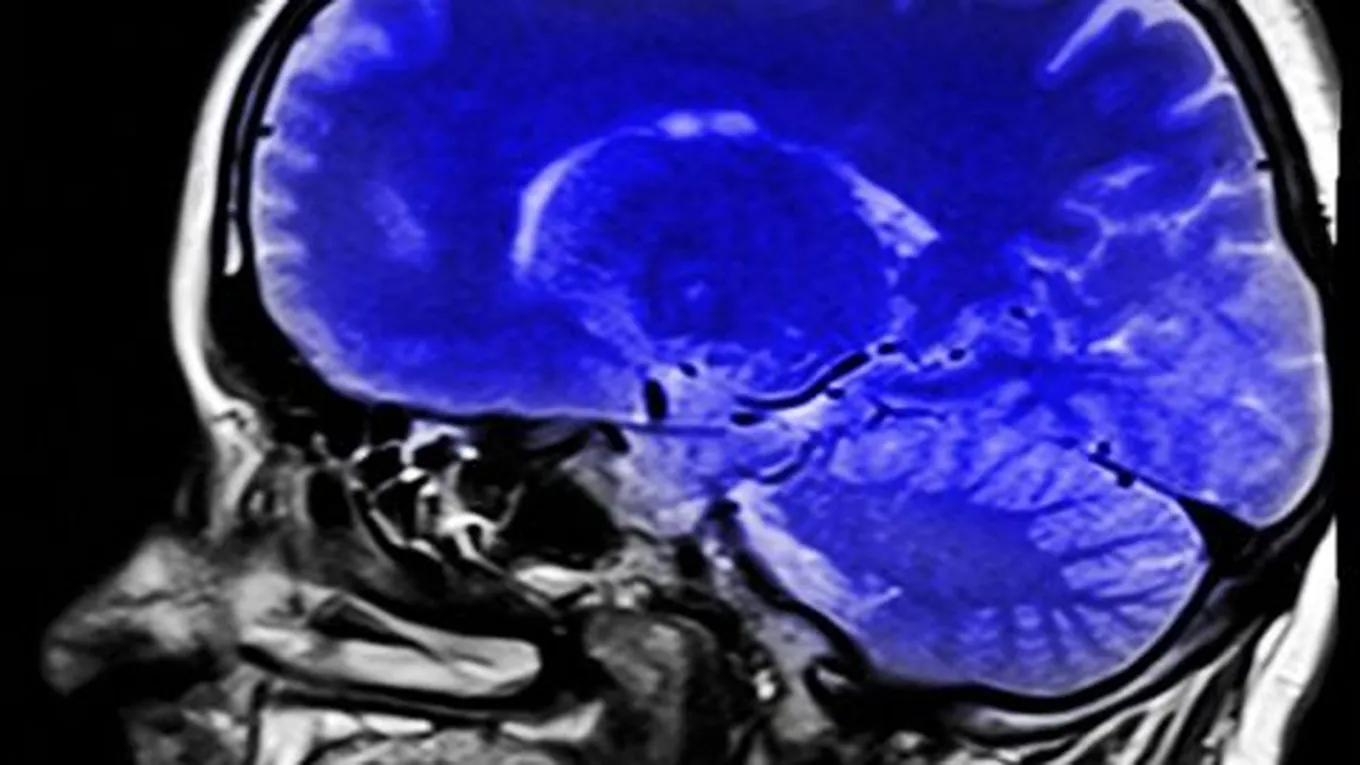

السكتة الدماغية الإقفاريةتُمثل السكتة الدماغية الإقفارية (بالإنجليزية: Ischemic stroke) النّوع الأكثر شيوعاً من السّكتات الدماغيّة، ويُعزى حدوثها إلى الانسداد

تُمثل السكتة الدماغية الإقفارية (بالإنجليزية: Ischemic stroke) النّوع الأكثر شيوعاً من السّكتات الدماغيّة، ويُعزى حدوثها إلى الانسداد الذي تُسبّبه الجلطة الدموية بما يحول دون تدفّق كميّاتٍ كافيّةٍ من الدم والأكسجين إلى الدماغ، وفي هذا السّياق يُشار إلى أنّ الجلطات الدمويّة تحدث في أغلب الأحيان في المناطق ذات الشرايين المُتضيّقة أو المسدودة بالرواسب الدهنيّة المُتشكّلة مع مرور الوقت؛ بحيث تُعرف هذه العملية بمصطلح تصلّب الشرايين (بالإنجليزية: Atherosclerosis). في الحقيقة، تُساهم العديد من العوامل في حدوث تضيّق الشرايين، وفيما يأتي بيان لأبرزها:[1]

السكتة الدماغيّة النزفيّة

يتمثل حدوث السّكتة الدماغيّة النزفيّة (بالإنجليزية: Hemorrhagic stroke) بانفجار الأوعية الدموية في الدماغ؛ بحيث قد يؤثر النّزيف في باطن الدماغ فيما يُعرف بنزيف المخّ (بالإنجليزية: Intracerebral hemorrhage)، وقد يحدث النّزيف على سطح الدماغ فيما يُعرف بنزيف تحت العنكبوتيّة (بالإنجليزية: Subarachnoid hemorrhage)، وتجدر الإشارة إلى أنّ ارتفاع ضغط الدم يُمثل السّبب الرئيسي لحدوث هذا النّوع من الجلطات؛ إذ قد يتسبّب ذلك بإضعاف الشرايين في الدماغ وجعلها أكثر عُرضة للانقسام أو التمزق، وفيما يتعلّق بعوامل الخطر التي تزيد من خطر ارتفاع ضغط الدم فيُمكن بيانُها على النّحو التالي:[2]